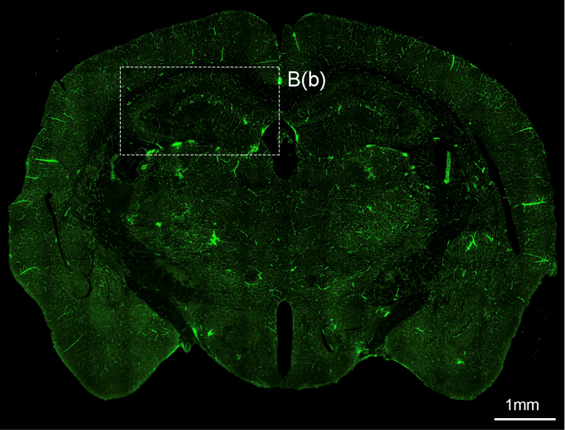

- 연구주제 : 뇌혈관장애-유래 인지기능 저하 및 근감소증 제어기전 연구

- 연구주제 : 뇌경색 동물모델 구축을 통한 뇌혈관 장애 및 염증제어 후보물질 발굴